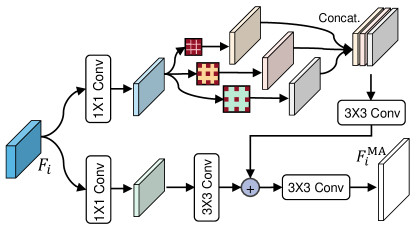

3.3 Scale-aware Convolution Module

Due to the same type of polyps having different scales, it is important to learn scale–correlated feature representations to boost the model in segmenting polyps. To achieve this, we propose a Scale-aware Convolution Module (SCM) to extract scale-aware features, which can exploit different scale-correlated information to enhance the feature representations. Specifically, is first passed through two convolutions to obtain and . Then, to learn scale-aware feature representations, we feed into three convolutions by using different dilated rates, respectively, thus we can obtain

where denotes a dilated convolution with a dilated rate of , followed by batch normalization with a ReLU activation. In this study, three different dilated rates, i.e., , are adopted. After that, the three scale-aware features (i.e., ) are concatenated, which is passed through a convolutional layer for adaptive aggregation to obtain the concatenated feature. At last, the concatenated feature is fused and the original feature , thus this process can be represented by

where denotes an element-wise addition operation. As a result, we obtain the scale-aware feature , which is regarded as the output of the -th SCM.

It is worth noting that our SCM can enhance multi-scale feature representations by utilizing different dilated convolutions, in which small-scale (with small dilated rates) and large-scale (with large dilated rates) features can be aggregated to handle the challenge of scale variation.